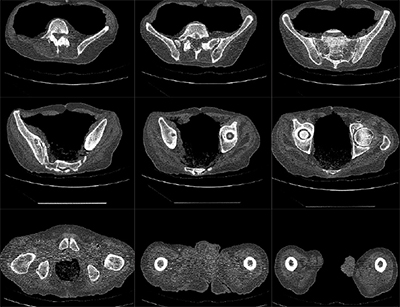

Mako Robotic-Arm Assisted Technology provides you with a personalized surgical plan based on your unique anatomy. First, a CT scan of the diseased hip or knee joint is taken. This CT scan is uploaded into the Mako System software, where a 3D model of your hip or knee is created. This 3D model is used to pre-plan and assist your surgeon in performing your joint replacement procedure.

In the operating room, your surgeon follows your personalized surgical plan while preparing the bone for the implant. The surgeon guides the robotic-arm within the pre-defined area and the Mako System helps the surgeon stay within the planned boundaries that were defined when the personalized pre-operative plan was created. In a laboratory study, Mako Total Knee Technology demonstrated accurate placement of implants to a personalized surgical plan.1 This study also showed that Mako Total Knee replacement demonstrated soft tissue protection to the ligaments around the knee.1 In patient and laboratory studies on Mako Total Hip and Partial Knee replacement, Mako Technology demonstrated accurate placement of implants to a personalized surgical plan.2-4